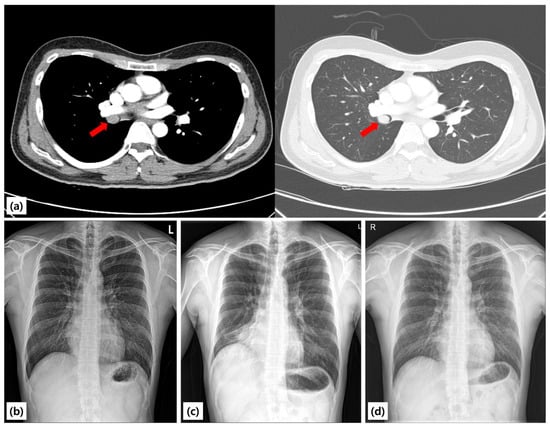

A 25-year-old never-smoking man with no comorbidities was referred to our hospital after an abnormal chest radiograph obtained during a routine occupational health screening earlier in the year. The film demonstrated right lung volume loss and an ill-defined opacity. A subsequent chest CT scan revealed a well-circumscribed endoluminal mass arising within the proximal right bronchus intermedius, causing near-complete luminal obstruction and associated distal atelectasis of the right middle and lower lobes (Figure 1). A chest radiograph taken in 2021 was entirely normal, suggesting that the lesion developed within the following three years. A chest radiograph taken in 2021 was entirely normal, suggesting that the lesion developed within the following three years. The patient denied cough, hemoptysis, chest pain, weight loss, fever, or recurrent respiratory infections. He reported only occasional exertional chest tightness during vigorous exercise, which he had not previously sought evaluation for. There was no family history of lung disease, tuberculosis, or malignancy.

The patient was observed overnight in the hospital. He had no hemoptysis, chest discomfort, or respiratory distress, and was discharged uneventfully the following day. Oral antibiotics and inhaled bronchodilators were not prescribed, as there was no evidence of infection or post-procedural bronchospasm. At one-week outpatient follow-up, he reported resolution of exertional symptoms, and chest radiography showed re-expansion of the right middle and lower lobes. Spirometry demonstrated normalization of FEV1 and FVC values, with complete resolution of the obstructive physiology (Figure 2). Baseline: FEV1 = 2.31 L (64% predicted), FVC = 2.72 L (68%), and FEV1/FVC = 0.85; Post-procedure: FEV1 = 3.65 L (101%), FVC = 3.82 L (98%), and FEV1/FVC = 0.96.

At three months, six months, and one year, surveillance bronchoscopy and chest CT scans were performed. All examinations demonstrated a widely patent right bronchus intermedius, with no evidence of residual or recurrent tumor (Figure 3). Spirometry remained normal, and the patient resumed unrestricted physical activity without limitation.

Figure 1. Chest radiographs and CT findings. (a) Pre-procedure chest CT scan showing a mass completely obstructing the proximal bronchus intermedius with distal atelectasis (red arrow). (b) Pre-procedure chest radiograph demonstrating volume loss of the right middle and lower lobes, manifested by elevation of the right hemidiaphragm and increased opacity in the right lower lung field, consistent with atelectasis. (c) Chest radiograph obtained two years earlier showing normal findings. (d) Post-procedure chest radiograph showing normalization of lung volume and resolution of atelectasis.